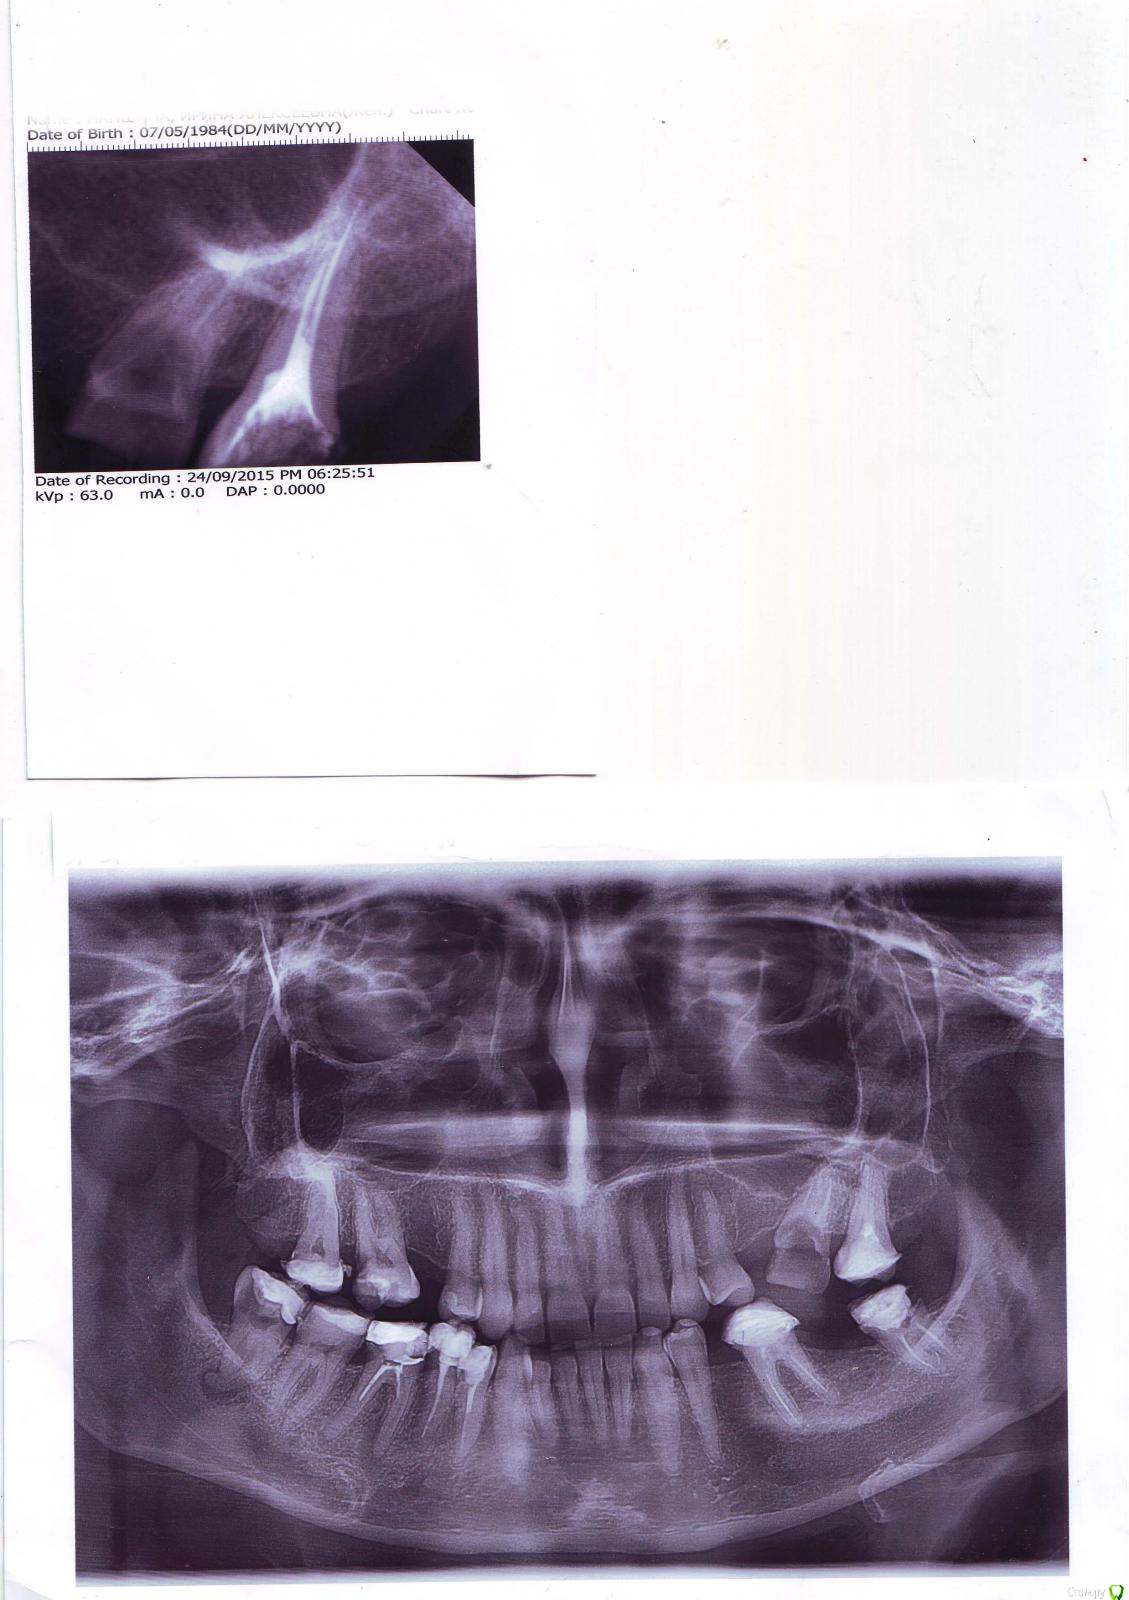

Арина74 Опубликовано 1 декабря, 2015 Поделиться Опубликовано 1 декабря, 2015 (изменено) Здравствуйте, уважаемые стоматологи! Посмотрите, пожалуйста, мой снимок и посоветуйте оптимальное протезирование.Мне 42 года, зубы бездумно удаляла, т.к. лечить боялась, а удалять нет..., поэтому вот что имею.На данный момент уже удалена нижняя правая 6, на снимке она еще есть. Маленький снимок это последний верхний зуб с левой стороны, снимок сделан после подготовки к протезированию.Первый ортопед (протезист) сначала хотела сделать вверху с обеих сторон: 6 и 7 под коронки и повесить консоль, чтобы закрыть 5-киВнизу: с левой стороны 8 и 6 под коронки и закрыть 7 и 5. С правой стороны: 8 удалить, 7 и 5 под коронки, 6 закрыть (мост)После лечения верней левой 7 (маленький снимок) и попытка подготовить 6 - сказала, что 6 не подходит ее надо удалять (как она объяснила, внутри все мягко), нижнюю 8-ку брать под коронку она передумала, поэтому у меня только один выбор - это импланты.Я пошла к имплантологу, его заключение : импланты - это не мой случай (зубы, кроме нижней 6 удалены давно, больше 15 лет назад, кости нет), стачивайте 4 (вверху) и устанавливайте мост. Когда я сказала, что 4 жалко, он был очень удивлен: чего их жалеть??? стачивайте и ставьте мосты!Сходила еще к двум ортопедам, они сказали, что проблемную, обломанную, верхнюю 6 можно попробовать подготовить под коронку и сделать первый вариант: без обточки верхних четверок и установить вверху консоли, внизу использовать слева 8 и установить мосты.Скажите, пож., правильный ли план протезирования? Консольные коронки - это вообще крепкая конструкция?Можно ли в моем случае использовать нижнюю 8 под коронку?И еще вопрос, после мостов, когда пройдет несколько лет, возможно будет установить импланты?Спасибо, большое! Изменено 1 декабря, 2015 пользователем Арина74 Ссылка на комментарий

Арина74 Опубликовано 1 декабря, 2015 Автор Поделиться Опубликовано 1 декабря, 2015 (изменено) Добавлю, верхняя 6-ка обломана по краю десны. Изменено 1 декабря, 2015 пользователем Арина74 Ссылка на комментарий

Ker Опубликовано 1 декабря, 2015 Поделиться Опубликовано 1 декабря, 2015 (изменено) 4.6 зря удалили, можно было перелечить.4.8 удалять4.7 посмотреть что с пломбой.4.4., 4.5 - коронки. в идеале переличить каналы.3.6 выглядит спокойно, в идеале перелечить.3.7 вкладка, коронка2.7 удалять, скорее всего.1.6 лечить "мосты" вполне можно поставить Изменено 1 декабря, 2015 пользователем Ker Ссылка на комментарий

Арина74 Опубликовано 1 декабря, 2015 Автор Поделиться Опубликовано 1 декабря, 2015 с 6 нижней так намучилась, был флюс, потом прошел, потом киста на десне. Врач хотела перелечить, после снимка сказала надо удалять...про 8 Вы имеете ввиду с правой или с левой стороны, или обе? левую под коронку нельзя? Извините, пожалуйста, я с нумерацией не пойму.а 2.7 и 1.6 это какие зубы? Спасибо! Ссылка на комментарий

Ker Опубликовано 1 декабря, 2015 Поделиться Опубликовано 1 декабря, 2015 4.8 это справа низ, левую думаю можно.2.7 это 7 слева верх1.6 это 6 справа верх Ссылка на комментарий

Ker Опубликовано 1 декабря, 2015 Поделиться Опубликовано 1 декабря, 2015 Спасибо, большое! Это 7- ка. Вверху у меня 8-к нет. По каналам 7-ки делали снимок с металлической иголкой, как я поняла проверяли каналы, но этих снимков у меня нет.У вас не восьмерок нет а шестерок. обе восьмерки наверху присутствуют.Внизу пока тоже. 1 Ссылка на комментарий

Арина74 Опубликовано 1 декабря, 2015 Автор Поделиться Опубликовано 1 декабря, 2015 (изменено) У вас не восьмерок нет а шестерок. обе восьмерки наверху присутствуют.Внизу пока тоже.Нет, наверху я удалила обе 5 и 8-ки, это я очень хорошо помню. 8-ки еще в молодости, а 5 обе после родов. Изменено 1 декабря, 2015 пользователем Арина74 Ссылка на комментарий

Ker Опубликовано 1 декабря, 2015 Поделиться Опубликовано 1 декабря, 2015 Нет, наверху я удалила обе 5 и 8-ки, это я очень хорошо помню. 8-ки еще в молодости, а 5 обе после родов.да, скорее всего. рассмотрел снимок получше. Ссылка на комментарий

Ker Опубликовано 2 декабря, 2015 Поделиться Опубликовано 2 декабря, 2015 Пожалуйста, если не трудно, еще раз напишите по верху, учитывая, что нет 5 и 8-к, а то я запуталась. Спасибо!Левую 6 удалять (скорее всего) справа перелечить 6, возможно депульпировать (удалить "нерв")пломбу на 7 тоже пересмотреть. Ссылка на комментарий